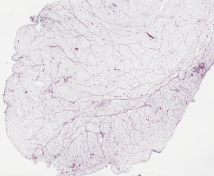

Category Train Validation Image Example

(Count) 1271 317 [Uncaptioned image]

(No-Count) Lipomas 703 176 [Uncaptioned image]

(No-Count) Non-neoplastic lesions 400 100 [Uncaptioned image]

(No-Count) Skin punch biopsies 180 45 [Uncaptioned image]

(No-Count) Skin&subcutaneous tissues 522 131 [Uncaptioned image]

Table 1: Biopsy slide classification data